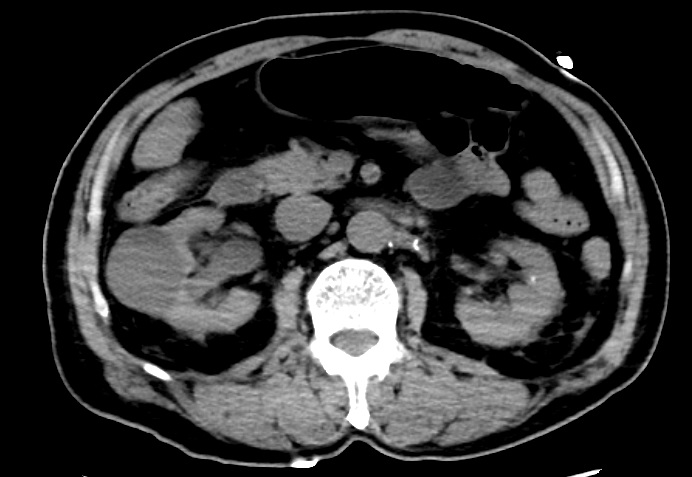

在有效的處理下,患者生命體征迅速穩(wěn)定,行CT檢查顯示雙腎周感染。